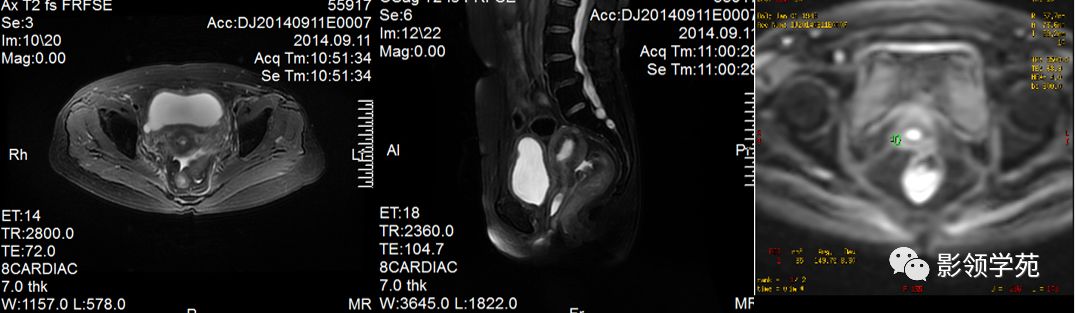

宫颈癌MRI表现

宫颈癌可表现为类圆形或不规则形肿块,在T2WI上表现为均匀或欠均匀的高信号,与正常宫颈基质及宫旁脂肪形成良好的自然对比。

- Ⅰ期肿瘤:侵犯宫颈基质,T2WI等信号肿块,宫颈管扩大及宫颈纤维基质中断

- Ⅱ期肿瘤:宫颈增大,宫旁肿块或宫旁脂肪组织内出现异常信号的粗线状影

- Ⅲ期肿瘤:侵犯至阴道下部,外延至盆壁,或出现肾积水。

IIB期